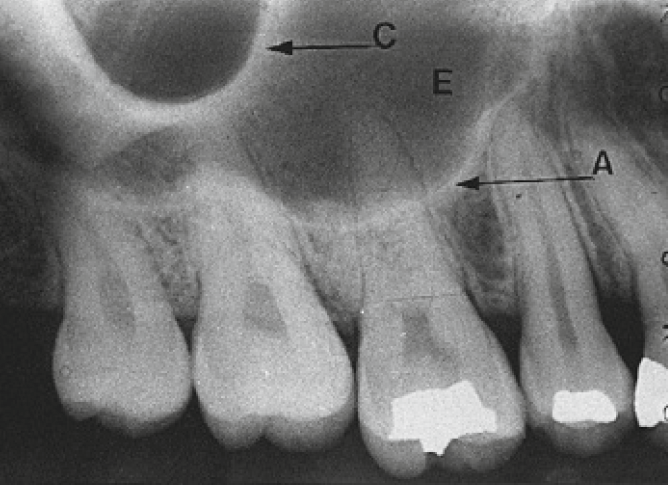

5. C arrow shows which anatomical structure ?

11. Which option is indicated by arrow E?

13. Arrow E showing which anatomical structure?

14. What is showing by E?